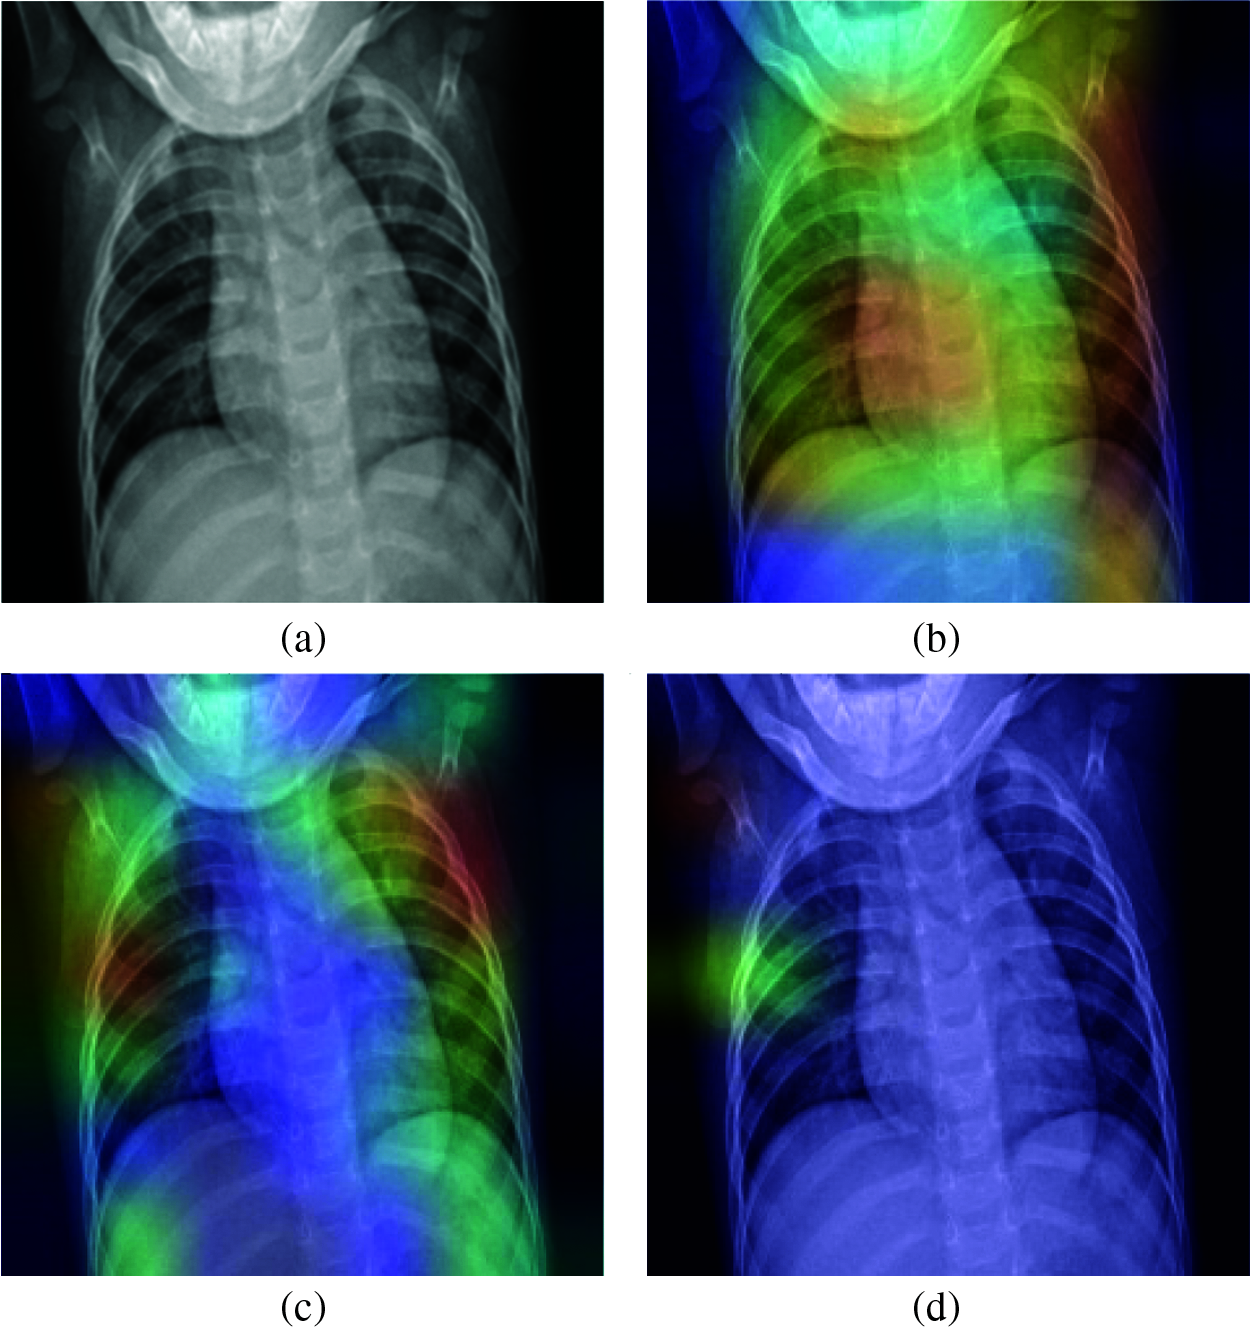

Figure 20: Grad-CAM visualization for predicting a real case of normal: (a) Original case (True class: Normal), (b) VGG-19 (Predicted class: Normal), (c) VGG-16 (Predicted class: Normal), (d) MobileNetV2 (Predicted class: Pneumonia)

In Fig. 20, the prediction of normal cases by different models shows that the VGG16 and VGG19 models correctly predicted the case as normal, but the MobileNetV2 model predicted it as pneumonia. The Grad-CAM visualization analysis confirmed that the VGG16 and VGG19 decisions were based on the correct pixels in the X-ray image, but the MobileNetV2 model focused on the wrong pixels in a small area of the image.